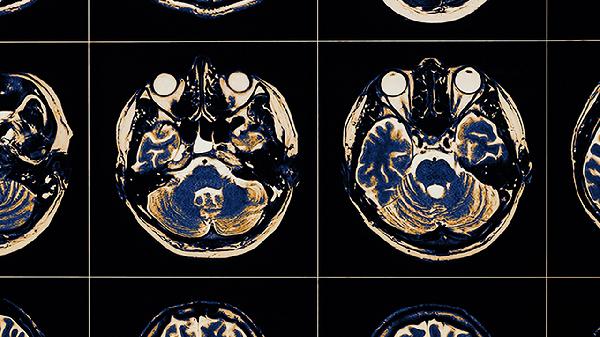

通过观察呼吸或身体感受锚定注意力,减少对焦虑想法的反刍。每天10分钟的正念练习能重塑大脑前额叶与杏仁核的功能连接,临床研究显示持续8周可降低皮质醇水平。初学者可使用专注力冥想或身体扫描等基础形式。

快走、游泳等有氧运动能促进内啡肽分泌,改善神经递质平衡。每周3次30分钟的中等强度运动即可调节自主神经系统功能,运动后90分钟内脑源性神经营养因子水平显著升高,有助于修复过度兴奋的神经回路。